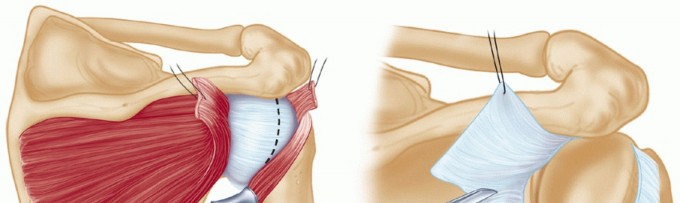

A longitudinal incision in the posterior axillary fold is made beginning at a point 2 cm medial to the posterolateral corner of the acromion and extending distally, following the posterior axillary line (TECH FIG 3).

- TECH FIG 3 • The posterior longitudinal incision begins about 2 cm medial to the posterolateral corner of the acromion and extends into the axillary crease.

- TECH FIG 4 • With the deltoid fibers bluntly split, a vertical incision is made directly through the infraspinatus while keeping a small stump of infraspinatus tendon attached laterally for reattachment later.

Third, the infraspinatus may be completely detached, leaving a 2-cm remnant of the tendon still attached for later repair (TECH FIG 4). It is tagged and carefully released from the underlying thin capsule. - Capsulotomy

A vertical capsulotomy is made on the humeral side with the arm in neutral rotation (TECH FIG 5A).

TECH FIG 5 • A. The infraspinatus is elevated as a single layer, exposing the underlying posterior capsule. A vertical capsulotomy is then made based on the humeral side from the 12 o'clock to the 6 o'clock position. B. Traction stitches are then placed as the medial capsule is divided horizontally, between the sutures, toward but not through the glenoid labrum.

With the vertical capsulotomy completed, two traction stitches are placed at the midposition and the capsule is horizontally divided, between the stitches, toward the middle of the glenoid rim, stopping 1 to 2 mm from the posterior glenoid labrum (TECH FIG 5B).